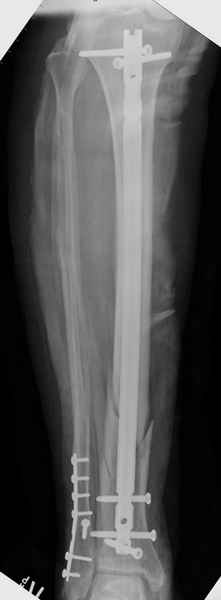

спрашивает что делать с больным который поступил недавно, фермер 55 лет падение при пьяной драке в баре, года два назад перенес операцию на лодыжке, на снимках и КТ перелом без вовлечения сустава,

Повреждение такой локализации, на которой применимы и аппарат (классический Илизарова или гибридный), пластина, особенно Locked Plate, и гвоздь с блокированием. В нашей клинике был бы выполнен закрытый интрамедуллярный остеосинтез. Желательно использовать гвоздь с возможностью провести более чем 2 обычных фронтальных винта в дистальном отломке.

Здесь мы использовали новый Synthes Nail с дополнительными дырками, в проксимальной части 4: по две косых и поперечные (один стандартный а другой динамический), в дистальной части две поперечные, прямая и косая. Вес больного более 120 кг, нагрузку начнем через месяц.

Получилось красиво, поздравляю. Вверху можно было ограничиться одним винтом во фронтальное статическое отверстие, зачем два 45-градусных?

При такий спирали задний край tibia может быть сломан - нет ли этого в данном случае? На всякий случай можно было ввести 1-2 винта 4,5 мм спереди назад мимо гвоздя. Хотя самый дистальный блокирующий винт, возможно, зацепил этот отломок. А какой тут диаметр гвоздя и locking винтов?